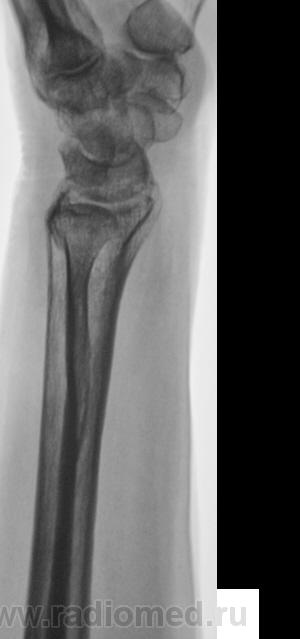

Травма.   Пациент направлен на рентгенографию лучезапястного сустава.